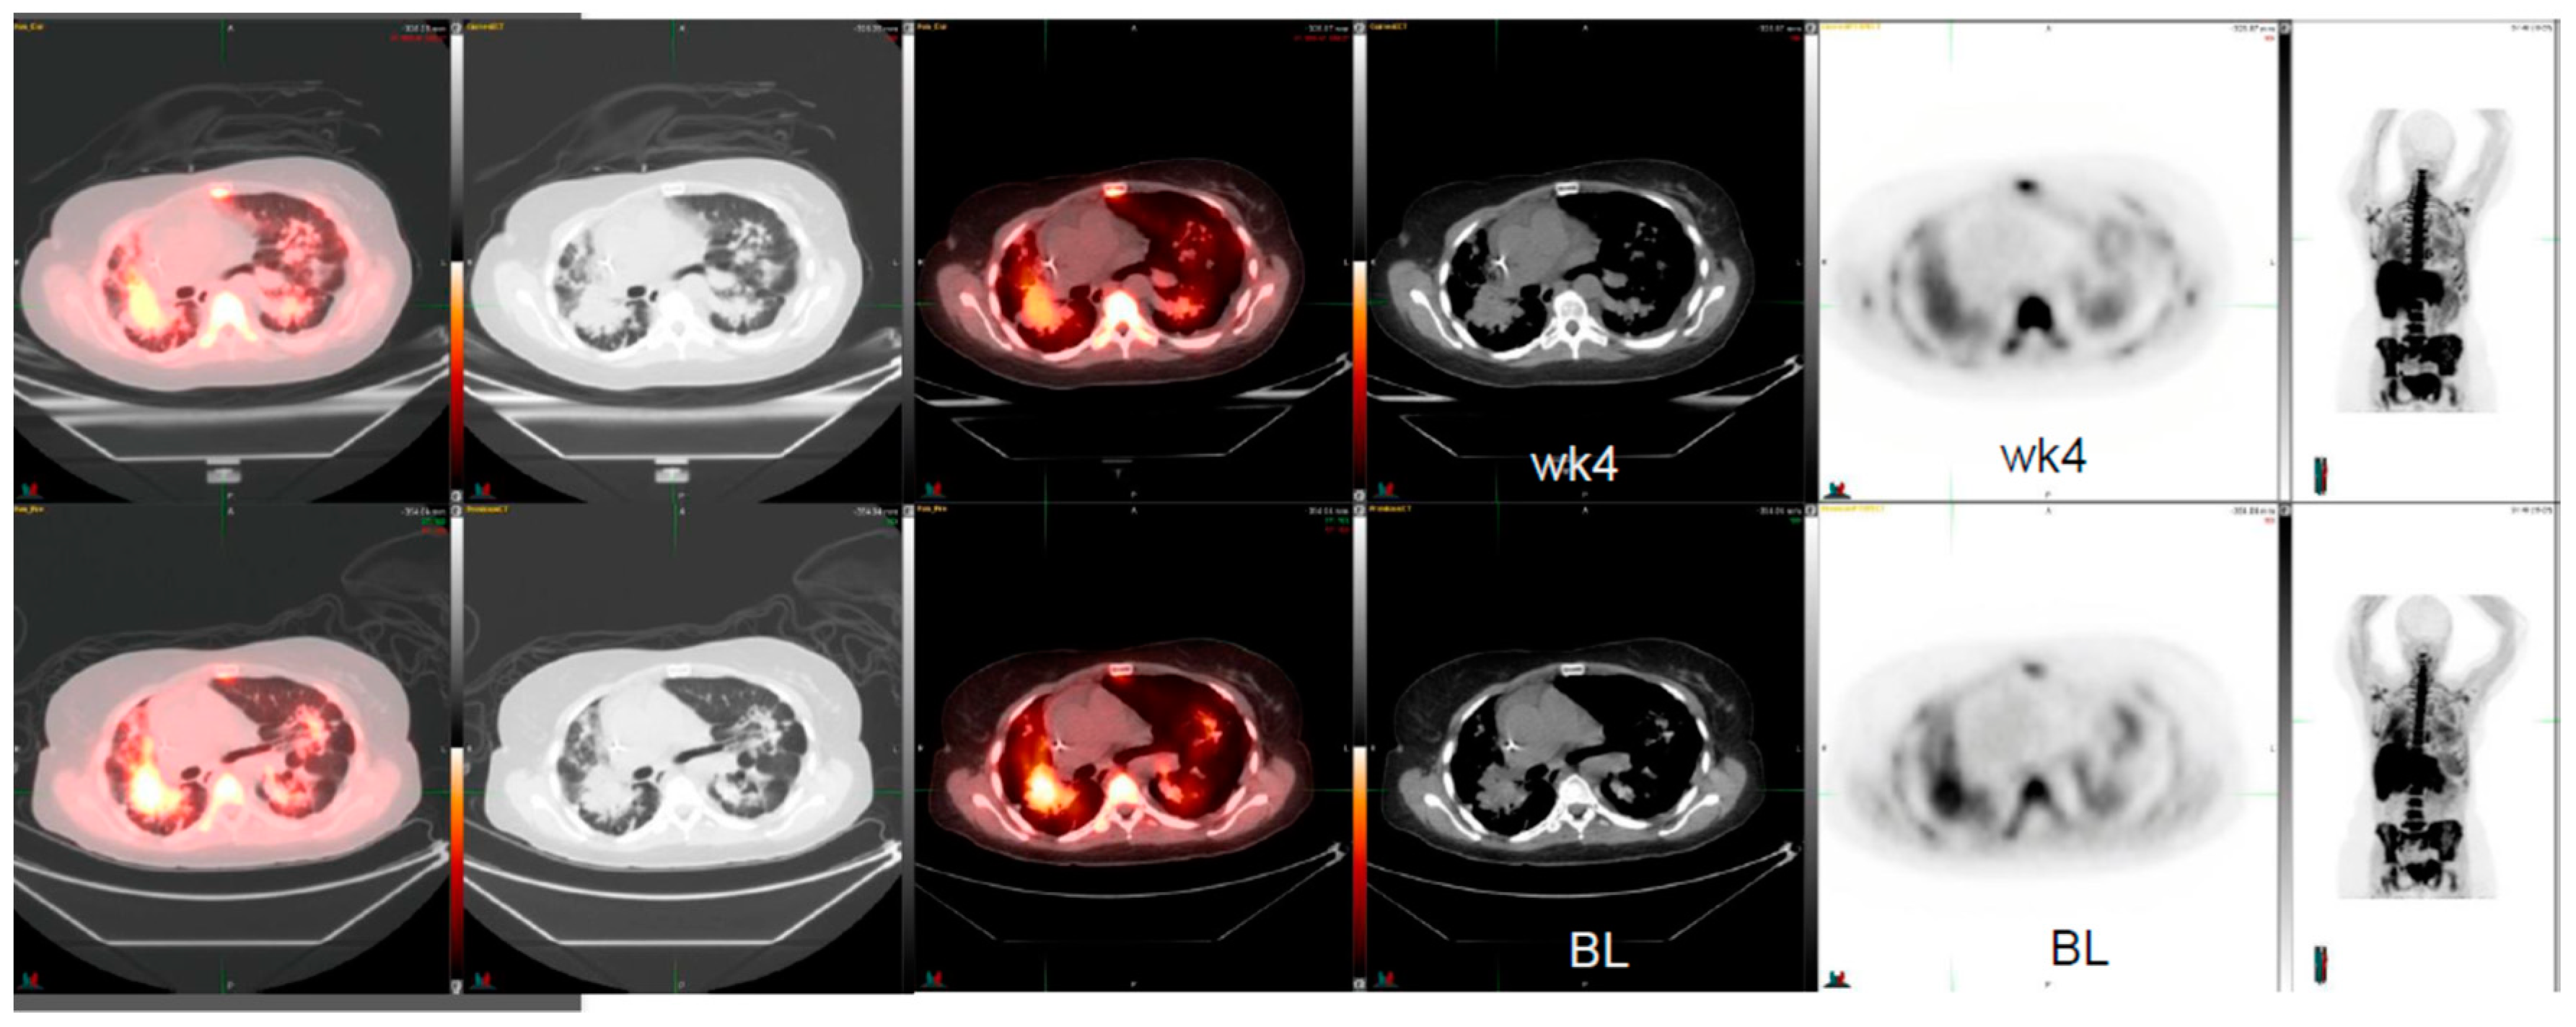

| Age/Gender/ New Therapy | Diagnosis | Previous Chemotherapy | 18F-FLT SUV Change | Comments |

|---|---|---|---|---|

| 49/male c-MET-inhibitor | small cell lung cancer | cisplatin, etoposide | −38% | FDG-change +2% CT-change 0 % |

| 51/female c-MET-inhibitor | lung adenocarcinoma | erlotinib, carboplatin, gemcitabine/docetaxel, pemetrexed, sorafenib, irinotecan, bevacizumab | −24% | EGFR positive CT-change +2% |

| 59/female MDM2 inhibitor | lung adenocarcinoma | cisplatin, vinorelbine, pemetrexed, cetuximab | −31% | EGFR negative CT-change -6% |